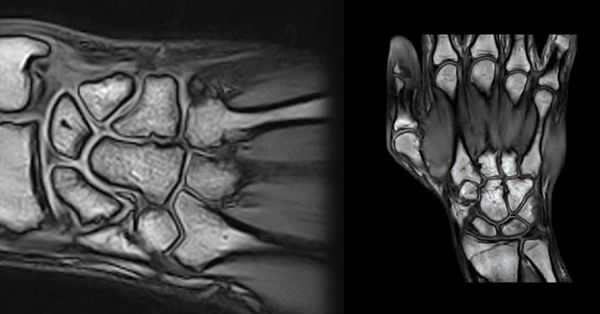

(Справа) На заднепередней рентгенограмме у этого же пациента визуализируется шиловидная кость у основания 3-й пятой кости. Ее проксимальный кортикальный слой имитирует перелом. Расположенные сверху сухожилия, проходящие через костное возвышение, могут раздражаться. (Слева) На осевой MPT STIR определяется запястно-пястный выступ с клиническими проявлениями. Тыльное возвышение исходит из основания 3-й пястной кости и имеет легкий отек.

(Справа) На осевой MPT STIR у этого же пациента, полученной на 5 мм проксимальнее первого изображения, определяется сигнал повышенной интенсивности, указывающий на теносиновит вокруг сухожилия разгибателя. Он является результатом повторного импиджмента и раздражения сухожилия при совершении запястьем нормального объема движений. (Слева) На сагиттальной КТ визуализируется мелкая шиловидная кость, расположенная за головчатой костью/3-м пястным суставом. Она была ошибочно принята за перелом после очень легкой травмы тыльной поверхности запястья.

(Справа) На осевой КТ видно взаимоотношение надполулунной с полулунной костью, «образующей сустав» с тыльным и лучевым кортикальным слоем полулунной кости.